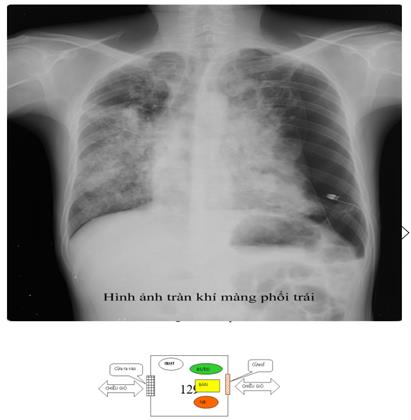

- Xquang phổi thường quy: hình ảnh trên phim X-quang gợi ý lao phổi tiến triển là thâm nhiễm, nốt, hang, có thể 1 bên hoặc 2 bên. Ở người có HIV, hình ảnh X-quang phổi ít thấy hình hang, hay gặp tổn thương tổ chức kẽ và có thể ở vùng thấp của phổi. X-quang phổi có giá trị sàng lọc cao với độ nhạy trên 90% với các trường hợp lao phổi AFB(+). Cần tăng cường sử dụng X-quang phổi tại các cơ sở y tế cho các trường hợp có triệu chứng hô hấp để sàng lọc lao phổi. Tuy nhiên cần lưu ý độ đặc hiệu không cao, nên không khẳng định chẩn đoán lao phổi chỉ bằng 1 phim X-quang phổi. Xquang phổi còn có tác dụng đánh giá đáp ứng với điều trị thử bằng kháng sinh thông thường trước khi chẩn đoán lao phổi không có bằng chứng vi khuẩn và để đánh giá kế quả điều trị lao sau 2 tháng và kết thúc điều trị.

Xquang ngực thấy hình mờ đậm thuần nhất, mất góc sườn hoành, đường cong Damoiseau. Siêu âm màng phổi có dịch.